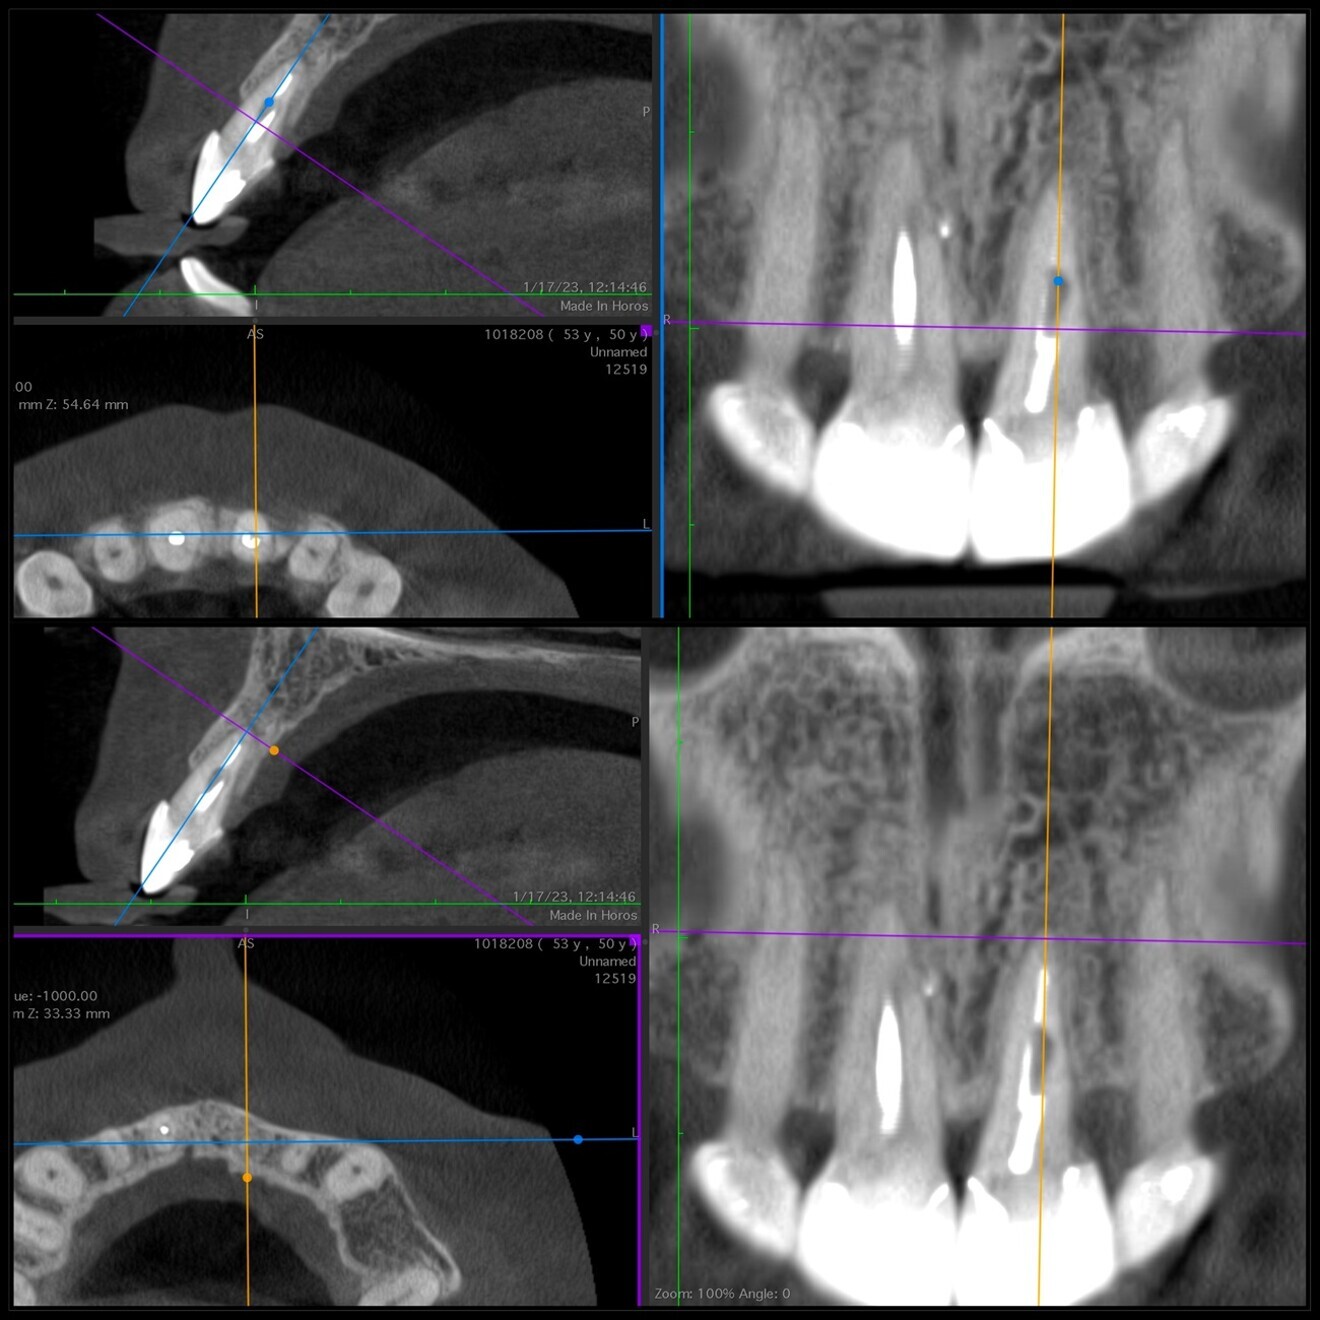

Radiographic examination conducted two years after the extrusion revealed good periapical healing and ongoing vertical bone growth at the interdental bone crest, mainly in the distal area (Fig. 5). It has been reported that a normal periodontal ligament contour may be observed three months postoperatively,6, 8, 20 and periapical repair and resolution of radiolucency are commonly seen six months later, as well as minimal marginal bone loss,6 often associated with bone damage incurred during the extrusion process. After two years of follow-up, complete repair of the periapical tissue and ongoing bone remodelling mainly in the area of the distal bone crest were observed (Fig. 6). The tooth remains asymptomatic, non-mobile, and fully functional aesthetically and biologically (Fig. 7). The radiographic situation after the four-year follow-up period showed stable results (Fig. 8).

Fig 6: Two-year follow-up CBCT scan showing complete periapical healing, bone remodelling in the distal area and no signs of resorption.